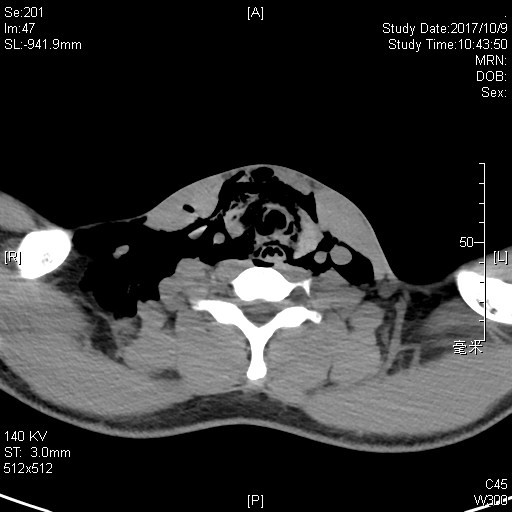

紧接其后,11月中旬,耳鼻咽喉头颈外科门诊迎来一位19岁的患者。小伙子在搬家时脚下一滑摔倒了,脖子不偏不倚卡在了一根金属横梁上。当时颈部并没有明显伤痕,但小伙子感到颈部疼痛难忍,说话声音哑了,还间断咳血;在来医院的路上,脖子越来越粗,而且感到严重的胸闷。接诊的顼晋昆和尹国平主治医师发现患者精神状态变差,呼吸逐渐不畅,颈部皮下有典型的捻发音(极细微而均匀的噼啪音),紧急为患者进行了喉镜检查、颈部CT扫描后,同样诊断为“颈部闭合性外伤、喉气管断裂伤”,气管断裂的位置位于声门下、环状软骨与第一气管软骨环之间。在麻醉科的配合下,耳鼻咽喉头颈外科医师第一时间为患者进行了全麻状态下的“气管切开术+I期喉气管断裂修复术”。术后10天,小伙子没有再出现呼吸困难或进食呛咳,拔除气管套管后康复出院。

图中显示气管断裂、颈部多发皮下气肿